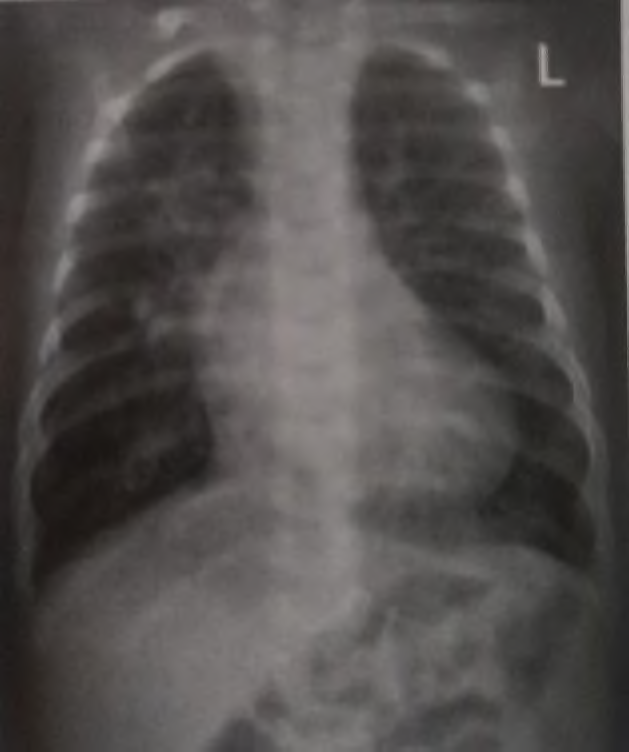

Recém-nascido com idade gestacional de 42 semanas, filho de mãe diabética, parto cesárea por pós-datismo e líquido amniótico meconial (+++/4+). Evolui com cianose central, FC: 120 bpm, FR: 65 ipm. Após ser colocado em halo respiratório com oferta de oxigênio a 100%, manteve cianose central e saturação de 60%. Gasometria arterial mostrou: pH: 7,25, pCO2: 42, pO2: 40, bic: 15, BE: -10 e SatO2: 57%. Realizada radiografia de tórax, conforme abaixo.

A conduta imediata neste momento é: